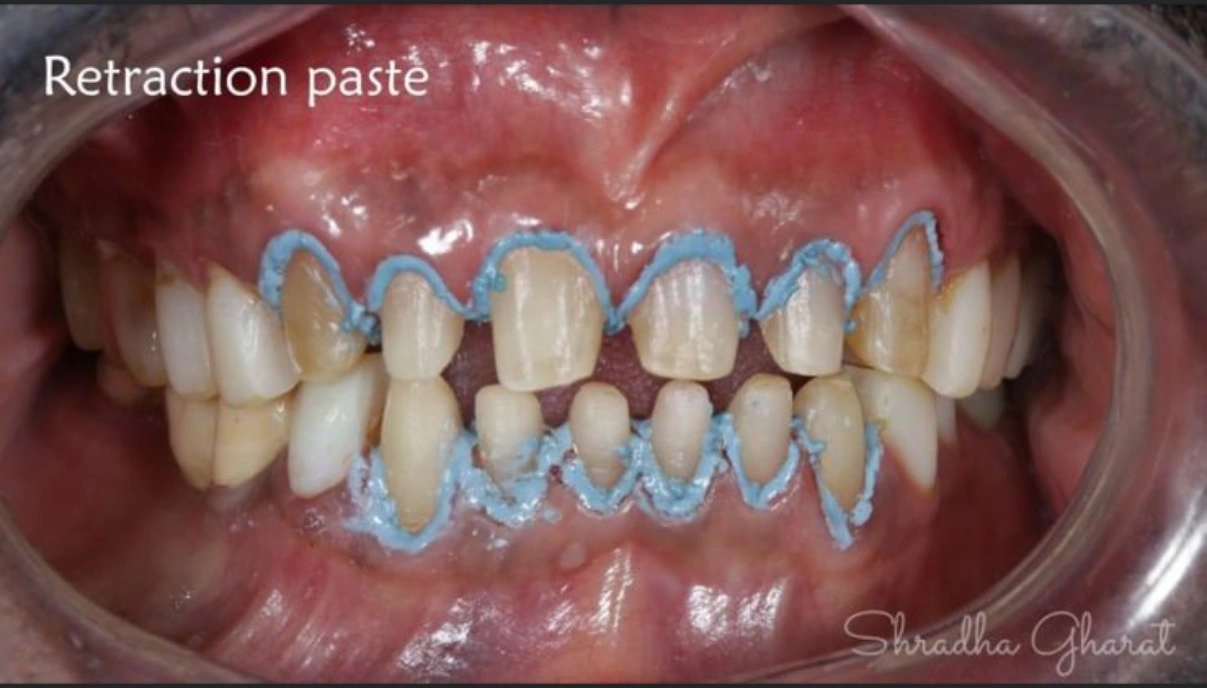

Full mouth rehabilitation includes restoration of lost tooth structure and bite. This technique sensitive procedure involves buildup of lost tooth enamel and dentin. Missing tooth can be replaced with Dental Implants or dental bridges. A Full mouth Reconstruction procedure is mainly indicated for patients with extreme tooth wear.

Full mouth rehabilitation (FMR) is a treatment plan for restoring function and function tolerance of dentition after surgery or dental restoration. It aims to restore dentition to the optimal point of function and esthetics of a healthy mouth. The treatment plan provides patients with a permanent smile that looks natural and bright.